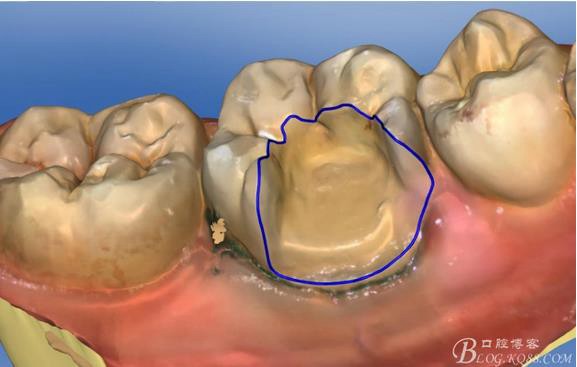

畫(huà)線(xiàn)是最關(guān)鍵的,線(xiàn)畫(huà)不好制出的修復(fù)體會(huì)出現(xiàn)邊緣缺損 或多 或少,醫(yī)生和技術(shù)配合

掃描 畫(huà)線(xiàn) 準(zhǔn)備研磨